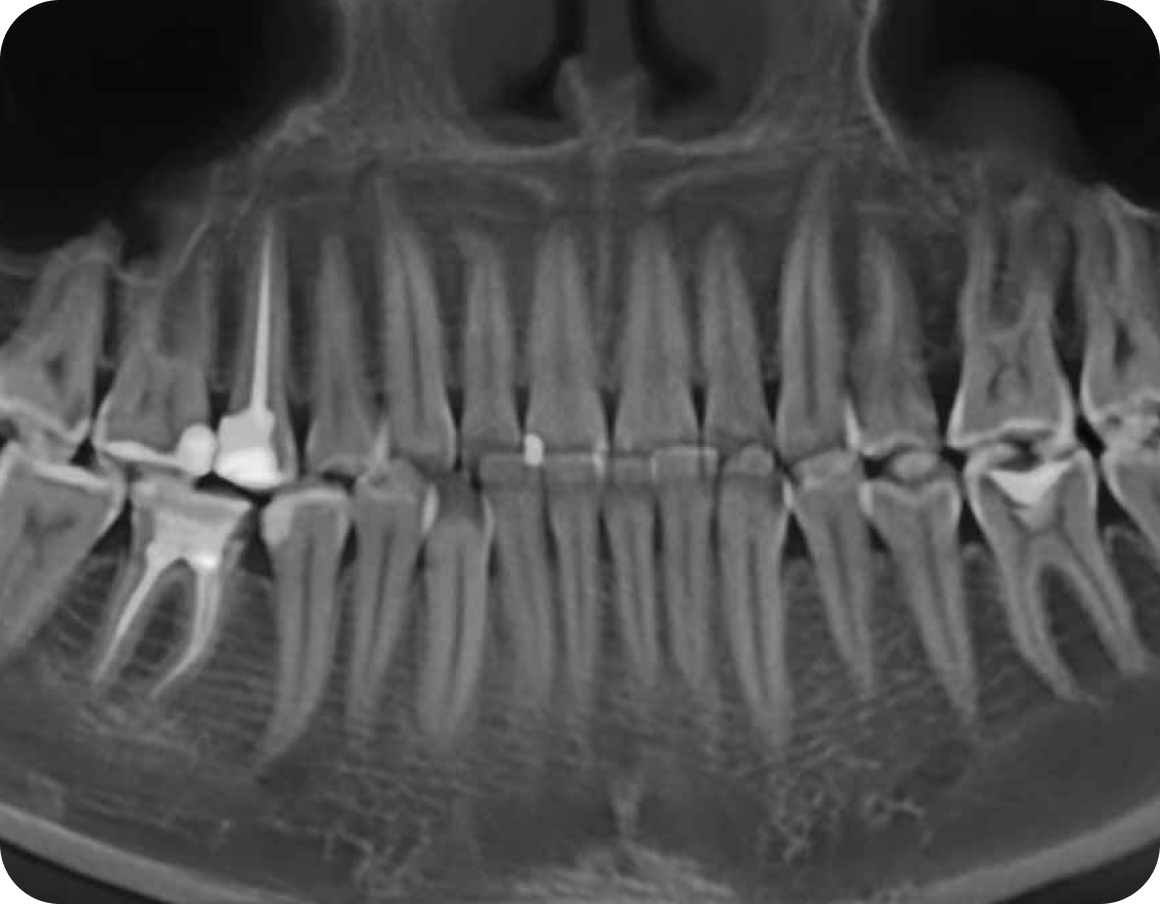

Компьютерная томография

Компьютерная томография - золотой стандарт лечения в клинике Дентамед

Мы делаем ее абсолютно каждому пациенту в рамках первичной консультации